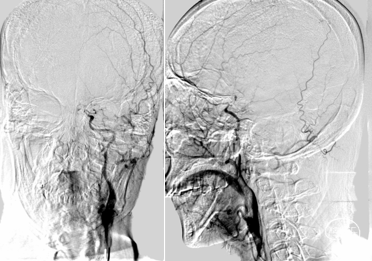

支架释放后发现远段大负荷血栓影,近端狭窄,狭窄不解除,远端血栓很难清除。

碎屑栓子取出,近端狭窄影响远端栓子清除,拟近端球扩,取栓后有小缝隙,留个路图,方便导丝通过。

2.5*15mm球囊6atm 压力。

球扩后造影,远端大负荷量血栓,抽吸效果更佳,且患者局麻操作,越快越好,操作越复杂风险越大,故更换器械。

AXS Infinity导管鞘结合AXS Catalyst 7颅内支持导管,导管鞘支撑裸奔到位,抽吸10s后明显落空,大量血栓。

AXS Infinity LS导管鞘结合AXS Catalyst 7颅内支持导管。导管鞘支撑,颅内支持导管送至基底动脉远端再次抽吸,多次抽吸无负压后结束抽吸 。